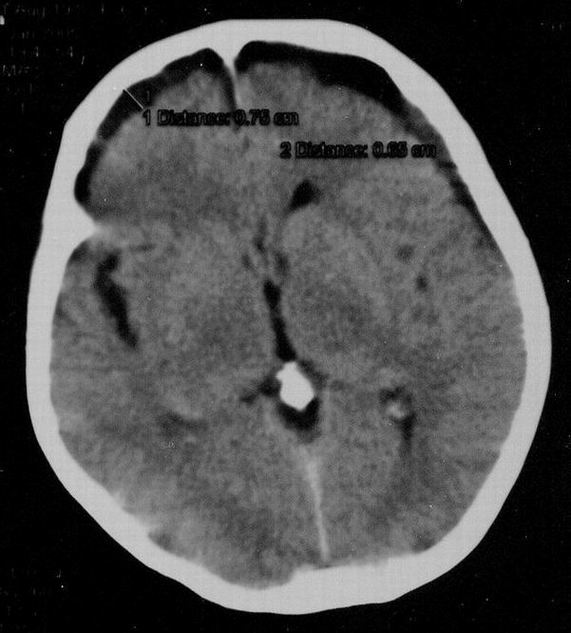

Субдуральная гигрома, Субдуральная гигрома-динамика |

Здравствуйте, коллеги. Хотелось бы обсудить субдур. гигромы, коими господа нейрохирурги объясняют свои оперативные вмешательства, при отсутствии на секции какой-бы то ни было морфологии. Но у нас так было раньше, теперь появилось чудо техники - компьютерный томограф. И вот "первая ласточка" - гигрома в лобно-височных отделах, вроде бы подтвержденная объективно. Или нет?